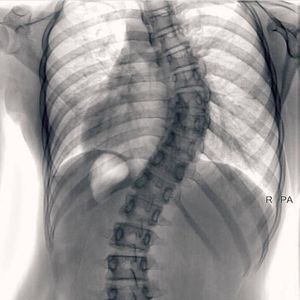

Scoliosis is a medical condition in which a person's spine has a sideways curve. The curve is usually "S"- or "C"-shaped.In some the degree of curve is stable, while in others it increases over time.Mild scoliosis does not typically cause problems, while severe cases can interfere with breathing.There is typically no pain present.